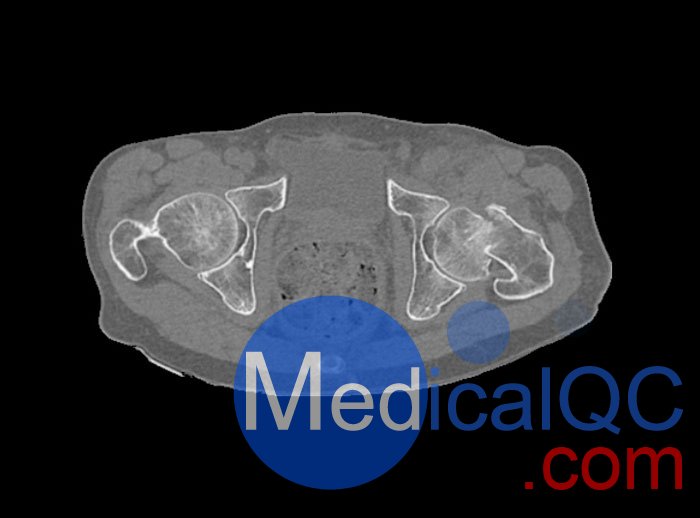

左側(cè)股骨頸移位骨折。

WEK54-01股骨頸骨折骨盆模型,WEK54-01骨盆模體提供了對(duì)軟組織和骨組織的詳細(xì)而逼真的模擬??障吨刑畛渲s-160HU的纖維素-聚合物復(fù)合材料。

骨骼和軟組織的逼真模擬。